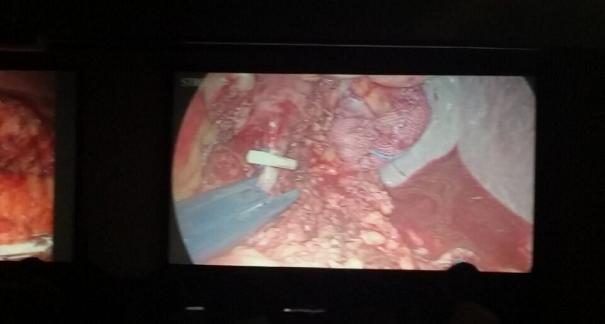

2015年10月23-25日,河北省醫(yī)學會肝膽外科學術年會在河北省石家莊市頤園賓館隆重召開。本次學術會議河北省醫(yī)學會特邀了北京301總院的胡明根教授、天津第一中心醫(yī)院的張雅敏教授、山西醫(yī)大醫(yī)院的趙浩亮、河北醫(yī)科大學第二醫(yī)院劉建華教授等國內(nèi)知名專家參會。參加會議的醫(yī)院達100余家,近300名肝膽外科的臨床專家和一線醫(yī)生們親臨會場,在此進行廣泛的學術交流。25號全天會議安排了五臺手術視頻演示,全體參會人員進行觀摩,并實時提問,進行手術交流。演示手術包括腹腔鏡胰、十二指腸切除術、腹腔鏡左、右半肝切除術、腹腔鏡門脈高壓癥的治療、兩鏡或三鏡聯(lián)合膽石癥的治療、開腹胰、十二指腸切除術、手術演示中多次使用了我公司產(chǎn)品速豐(可吸收止血結扎夾),產(chǎn)品使用滿意度受到專家們的一致好評。